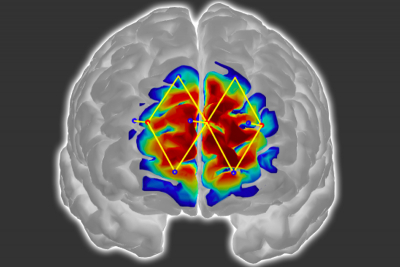

Researchers from MIT and elsewhere have developed a system that measures a patient’s pain level by analysing brain activity from a functional near infrared spectroscopy (fNIRS) device. The system could help doctors diagnose and treat pain in unconscious and non-communicative patients, which could reduce the risk of chronic pain that can occur after surgery.

The researchers use only a few fNIRS sensors on a patient’s forehead to measure activity in the prefrontal cortex, which plays a major role in pain processing. Using the measured brain signals, the researchers developed personalised machine-learning models to detect patterns of oxygenated haemoglobin levels associated with pain responses, which predicted whether a patient is experiencing pain with around 87 % accuracy.